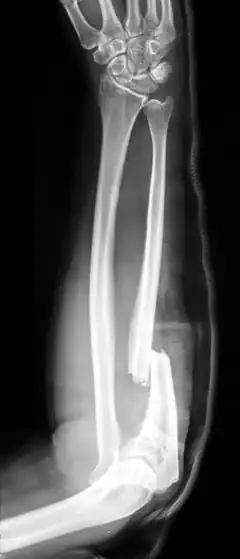

Ulna fractures

An isolated fracture of the ulna, also called a night stick fracture, is usually a sign of having defended oneself while protecting the head from being hit by a blunt object.[4][2] If associated with dislocation of radial head, it is called a Monteggia fracture, which can then be further classified according to the direction of displacement of the head of the radius at the elbow.[2]

-

Monteggia fracture -

Updisplaced isolated ulna fracture